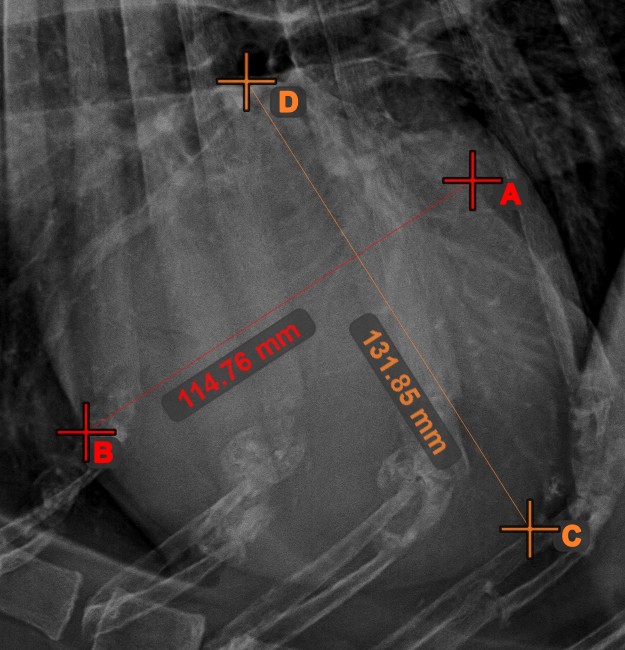

Angle of Lines

Calculate the angle between two independent or intersecting lines by using the Angle of Lines tool.

Select the tool from the left toolbar and assign it to one of the available mouse buttons. Start by selecting the first line from the ones already drawn on the scene, or place the start and end points to create the line. Follow the same steps for the second line of the measurement. The angle between the two lines will be automatically calculated.

Modify the start and end points of both lines by using the Select/Move Item tool. The angle between the two lines will be automatically recalculated.

Information

If two lines do not intersect directly, the angle of their extended projections on the scene will be calculated.

../_images/image7.jpg ../_images/image312.jpg